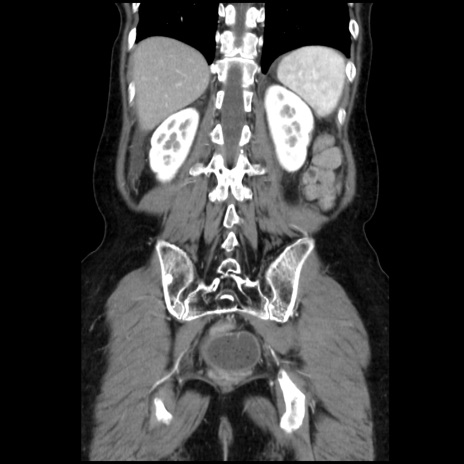

症例32(冠状断像)

【症例】40歳代 女性

【主訴】上腹部痛、嘔気・嘔吐

【現病歴】約9時間前頃から急に上腹部痛、嘔気、嘔吐が出現。改善しないため救急要請。

【既往歴】子宮頚癌(広汎子宮全摘術、放射線療法)、腸閉塞

【身体所見】腹部:平坦、軟、腸雑音亢進、上腹部を中心に腹部全体に圧痛あり。

【データ】WBC 8400、CRP 0.03